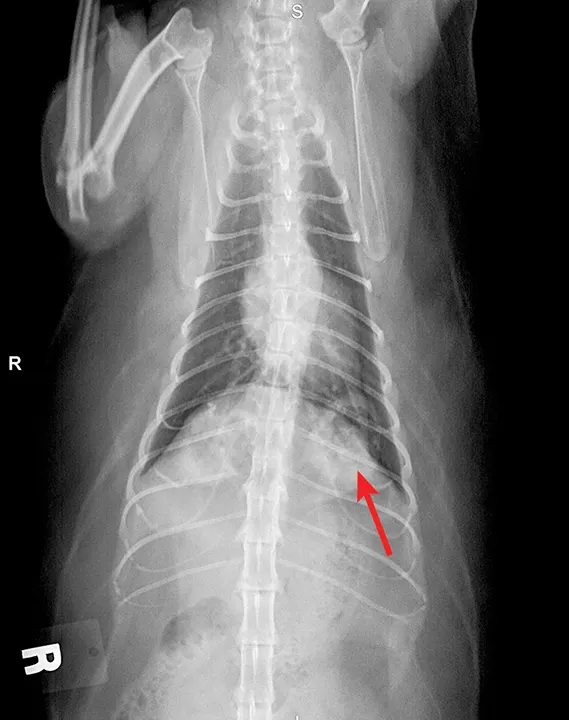

Lipid pneumonia may be appreciated in cats secondary to exogenous inhalation of oil (eg, mineral oil) or endogenous generation secondary to obstructive pulmonary disease (eg, bronchial disease, neoplasia). Radiographic features vary widely and can include diffuse interstitial, bronchointerstitial, or nodular patterns (Figure 7). Pleural effusion may be noted. These findings may represent the underlying obstructive disease.36,37

FIGURE 7

Endogenous lipid pneumonia confirmed on lung biopsy (orange arrow, biopsy site). The origin of the lipid pneumonia could not be identified in this case. Note the patchy unstructured interstitial opacities (red arrows).